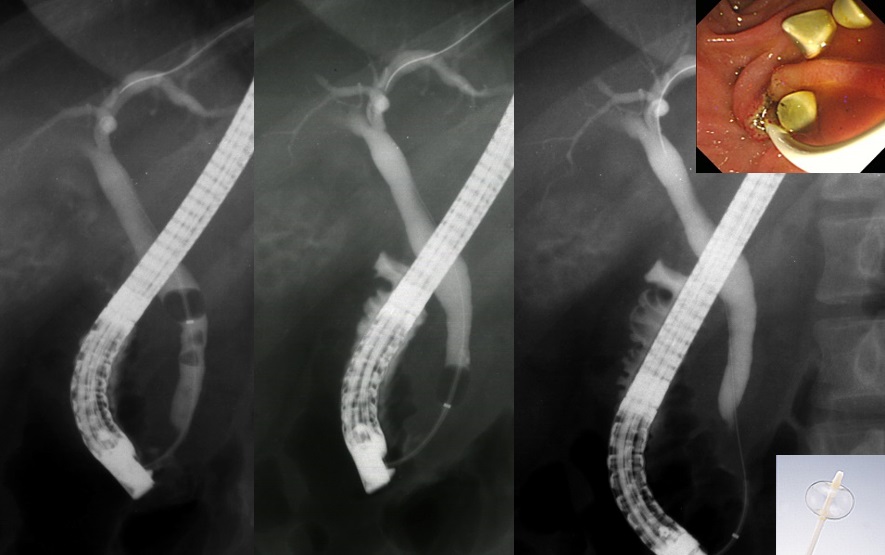

大腸ポリープ切除術、早期癌に対する内視鏡的粘膜剥離術、胃潰瘍などからの出血に対する内視鏡的止血術、食道静脈瘤からの出血に対する結紮術、アニサキス(寄生虫)や薬パッケージの誤飲に対する異物摘出術など。また胆道・膵臓系では、内視鏡を用いた胆石除去や、胆道感染や癌に伴う黄疸に対する内視鏡的な減黄術(ステント留置術)など各種行っております。

『内視鏡を用いた胆管結石除去術』